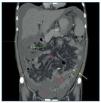

Figura 4.Tomografía computarizada abdominopélvica tras administración de contraste intravenoso, reconstrucción coronal, corte más anterior que el de la figura 3. Se observan calcificaciones «en sábana» del peritoneo parietal (flecha amarilla) y del peritoneo visceral (flechas verdes), conglomerados de calcificaciones del peritoneo visceral (flecha roja), engrosamiento del mesenterio de las asas intestinales (flecha rosa) por el desarrollo de membranas fibróticas que retraen las asas de intestino delgado adyacentes, y ascitis loculada (asteriscos rojos).